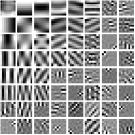

We pre-learn MARS models with different numbers of layers (depths) with transforms. The models are learned from overlapping patches extracted from five XCAT phantom slices. The number of pixels and the number of overall training patches are about and , respectively. The training slices are displayed in the supplement (Fig. 13). The patch stride is . We choose , , , , and layers, respectively, during training, which corresponds to ST, MARS2, MARS3, MARS5, and MARS7 models. We initialize the MARS learning algorithm with the 2D DCT matrix for the transform in the first layer and identity matrices for transforms in deeper layers. For each model, we ran 1000 to 1500 iterations of the block coordinate descent training algorithm to ensure convergence. We choose for ST, , , for MARS2, , , , , for MARS3, , , , , , , , , for MARS5, , , , , , , , , , , , , for MARS7. Fig. 3 shows some of the learned transforms, with each transform matrix row displayed as a square patch for simplicity. The first layer transform in the models typically displays edge-like and gradient filters that sparsify the image. However, with more layers, finer level features are learned to sparsify transform-domain residuals in deeper layers. Nonetheless, the transforms in quite deep layers could potentially be more easily contaminated with noise in the training data, since the main image features are successively filtered out over layers.